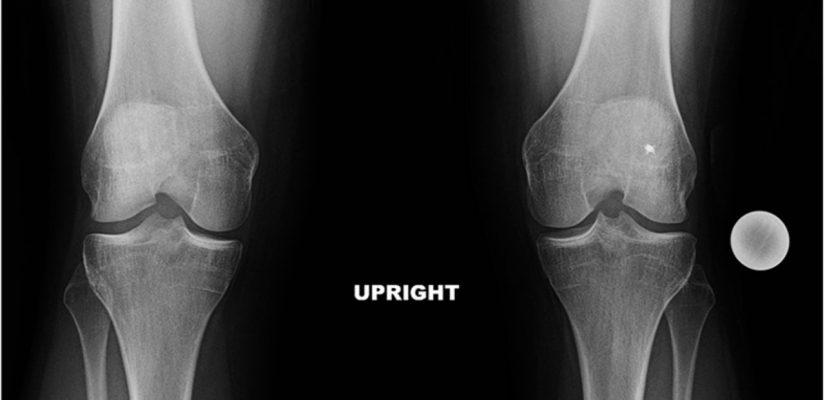

Ce este reumatismul degenerativ și când solicită atenţie imediată

Reumatismul degenerativ este un termen folosit pentru afectarea progresivă a articulaţiilor, care se manifestă prin durere, rigiditate și reducerea mobilităţii. Semne care indică nevoie de evaluare promptă includ durere severă bruscă, tumefacţie marcată, febră asociată cu simptome articulare, pierdere rapidă a funcţiei sau semne de infecţie.